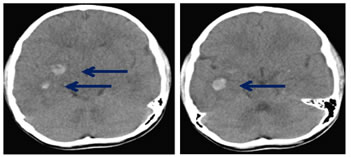

- CEREBRAL CONTUSION

- Characteristic location is adjacent to bony protuberance. Anterior frontal lobe and temporal lobe are the most frequently affected regions from cerebral contusion (Fig 13).

- Generally multifocal and bilaterally, but focal contusion may also occur adjacent to depressed skull fracture24.

- CT may be normal in the early phase or patchy, ill-defined lesions may be seen ashyperdense foci. CT scan can be subtle due to Beam Hardening artefact.

- CT scan findings can be normal or minimally abnormal because the partial volumes between the dense micro-hemorrhages and the hypodense edema can render contusions iso-attenuating relative to the surrounding brain tissue23,22

- "Coup" lesion; damage occurs at site of impact. "Countercoup" lesion; damage occurs at the opposite site of impact.

- Petechial hemorrhage may coalescence and become hematomas. Herniation may occur due to mass effect of hematoma24.

Figure 13: Axial NECT scan: A 10-year old boy was presented after a road traffic Accident. Hemorrhagic contusions seen involving right lentiform nucleus, right medial temporal cortex and right capsuloganglionic region.